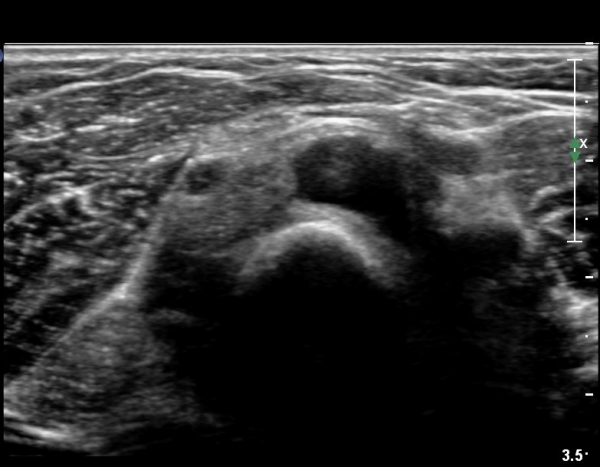

Èİñ°£ ½Å°æ Á¾´Ü¸é°Ë»ç¿¡¼­ ³¶Á¾¿¡ ÀÇÇÑ Èİñ°£ ½Å°æ ¾Ð¹Ú°ú  Èİñ°£ ½Å°æÀÇ ºÎÁ¾ÀÌ °üÂûµÈ´Ù(»çÁø 7).

out of plane À¸·Î ³¶Á¾ ÈíÀÎÀ» À§ÇØ ÁÖ»ç¹Ù´ÃÀÌ ³¶Á¾³»¿¡ À§Ä¡ÇÑ ¸ð½À(»çÁø 8)

³¶Á¾ ÈíÀÎ ÈÄ ³¶Á¾ÀÌ °ÅÀÇ º¸ÀÌÁö ¾Ê´Â ¸ð½À(»çÁø 9, 10)